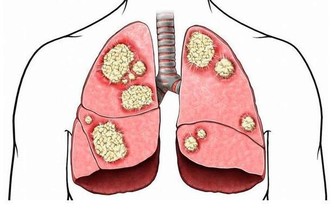

稍一運動就氣喘

男人向來比女人運動細胞發展得好,在各種體育項目中,男性都是比女性多的。但是現在的辦公室生活讓男人們的肌肉開始鬆懈,他們不再參加運動,甚至連周末都是在家補覺。有些男人稍一運動後就氣喘吁籲,而且持續時間比較長,這代表你的心臟調節能力越來越低,心臟的肌肉老化、彈性也在慢慢減弱,很容易出現心血管疾病。